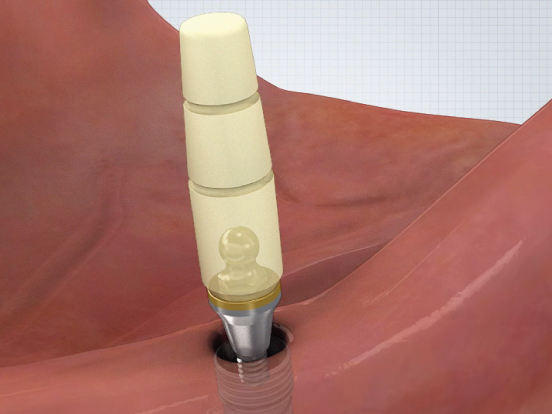

부분 상세설명 소모품교체 없음

소모품교체 없음Titanium housing과 Zirconia ball, Nitinol pan spring으로 이루어져 있어 소모품 교체 없이 장기간 사용이 가능하다.

Fixture 보호

Fixture 보호Locking 시 지대주와 housing 사이에 0.8mm 가량의 공간이 부여되어 의치 기능 시 연조직의 위축량을 보상함으로써 지대주에 가해지는 힘을 줄일 수 있다.

편측 20도 각도 보상

편측 20도 각도 보상지대주의 groove와 housing ball & spring이 체결되는 ‘EZ LOCKING 방식’에 의해 fixture의 식립각도를 20도까지 보상할 수 있다. (각도별 housing positioner 이용)